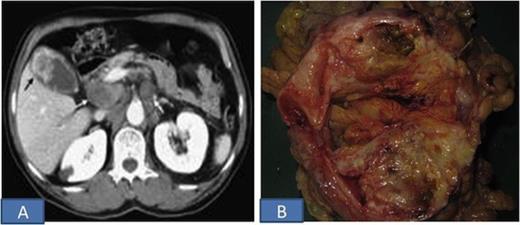

A 55-year-old woman presented with a 12 month history of intermittent right upper quadrant pain, anorexia, and weight loss. A physical examination revealed a non-tender and hard mass ~ 5x4 cm in the right upper quadrant of her abdomen. Laboratory examinations showed a normal leukocyte count, normal haemoglobin levels and liver function tests as well as a normal urine analysis. The serum levels of carcinoembryonic antigen and carbohydrate antigen 19-9 were within the normal reference range. Her family history and medical histories were unremarkable. Ultrasound Abdomen showed a 5-cm irregularly shaped heterogeneous mass in the gallbladder. On Computed tomography, a partially dilated gall bladder with multiple calculi and heterogeneously enhancing solid soft tissue density mass in the region of fundus with mild IHBR dilatation was seen. Liver and adjacent organs were all normal (Figure 1A).

The patient underwent cholecystectomy & wedge resection of the liver with resection of transverse colon and paraduodenal lymph nodes. Intra-operatively, a hard mass in the fundal region of gall bladder, adherent to the transverse colon was seen. Grossly, the tumor measured 7x5x3 cm and was solid grey-white (Figure 1B). The tumor was adherent to the colon but not infiltrating the wall of colon or underlying liver. Microscopic sections showed features of sarcomatoid carcinoma with focal squamous differentiation (Figure 2). The tumor cells were immunopositive for cytokeratin and vimentin. The tumor infiltrated into the adventitia of colon, however muscularis propria and mucosa were free of tumor. The underlying liver parenchyma, resected margins of liver, intestine, cystic duct and eleven lymphnodes dissected from specimen were free of tumor. Paraduodenal lymph nodes were also free of tumor.

A. CECT Abdomen shows soft tissue density in the region of fundus; B. Cut surface of the resected specimen showing a large variegated tumor in gall bladder